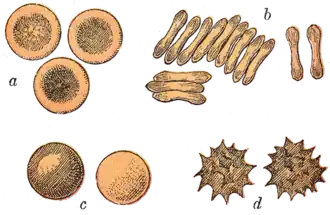

Mammals

The red blood cells of mammals are typically shaped as biconcave disks: flattened and depressed in the center, with a dumbbell-shaped cross section, and a torus-shaped rim on the edge of the disk. This shape allows for a high surface-area-to-volume (SA/V) ratio to facilitate diffusion of gases.[16] However, there are some exceptions concerning shape in the artiodactyl order (even-toed ungulates including cattle, deer, and their relatives), which displays a wide variety of bizarre red blood cell morphologies: small and highly ovaloid cells in llamas and camels (family Camelidae), tiny spherical cells in mouse deer (family Tragulidae), and cells which assume fusiform, lanceolate, crescentic, and irregularly polygonal and other angular forms in red deer and wapiti (family Cervidae). Members of this order have clearly evolved a mode of red blood cell development substantially different from the mammalian norm.[10][17] Overall, mammalian red blood cells are remarkably flexible and deformable so as to squeeze through tiny capillaries, as well as to maximize their apposing surface by assuming a cigar shape, where they efficiently release their oxygen load.[18]

Many diseases involving red blood cells are diagnosed with a blood film (or peripheral blood smear), where a thin layer of blood is smeared on a microscope slide. This may reveal poikilocytosis, which are variations in red blood cell shape. When red blood cells sometimes occur as a stack, flat side next to flat side. This is known as rouleaux formation, and it occurs more often if the levels of certain serum proteins are elevated, as for instance during inflammation.